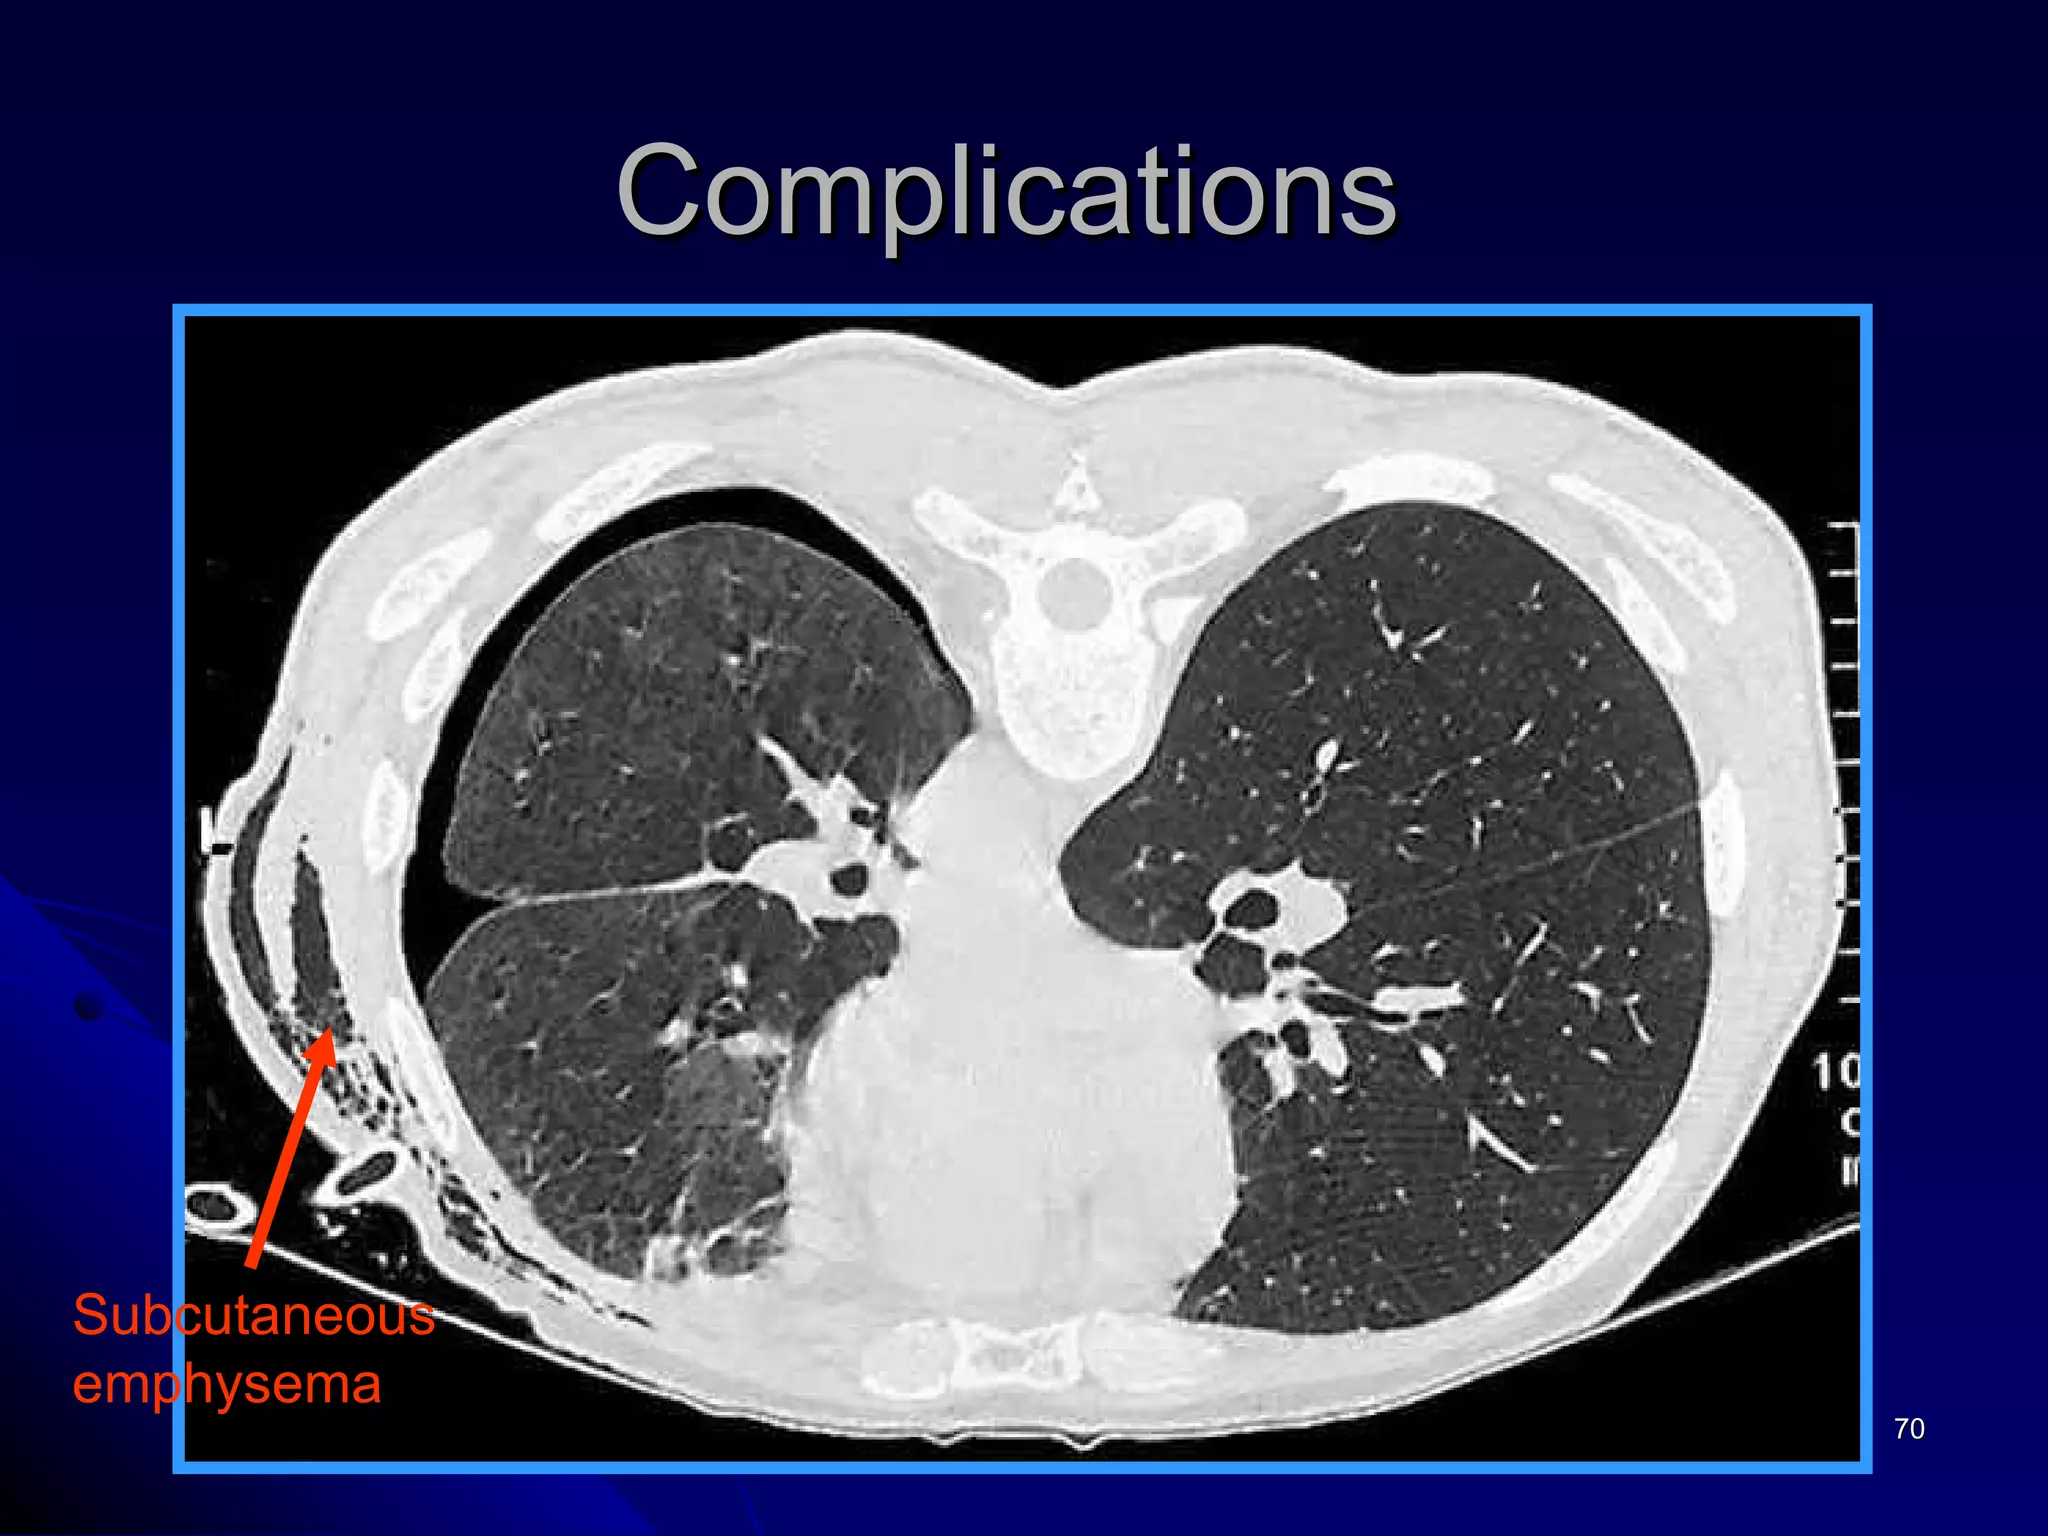

Complications of intercostal tube drainage Penetration of major organs Lung, stomach, spleen, liver, heart and great vessels Occur more commonly when a sharp metal trocar is inappropriately applied Pleural infection Empyema, the rate of 1% Surgical emphysema  Subcutaneous emphysema

Complications

Mediastinal and subcutaneous emphysema Alveoli rupture, the air enter into pulmonary interstitial, and then goes into mediastinal and subcutaneous tissues  After aspiration or intercostal chest tube insertion, the air enters the subcutaneous by the needle hole or incision  Physical exam – crepitus is present  Complications

Complications  Pneumomediastinum  Pneumocardium Pneumoperitoneum Surgical emphysema

Complications  Subcutaneous  emphysema

CT scanning Smallpneumothorax Subcutaneous emphysema

Complications of intercostaltube drainage Penetration of major organs Lung, stomach, spleen, liver, heart and great vessels Occur more commonly when a sharp metal trocar is inappropriately applied Pleural infection Empyema, the rate of 1% Surgical emphysema Subcutaneous emphysema

Mediastinal and subcutaneousemphysema Alveoli rupture, the air enter into pulmonary interstitial, and then goes into mediastinal and subcutaneous tissues After aspiration or intercostal chest tube insertion, the air enters the subcutaneous by the needle hole or incision Physical exam – crepitus is present Complications